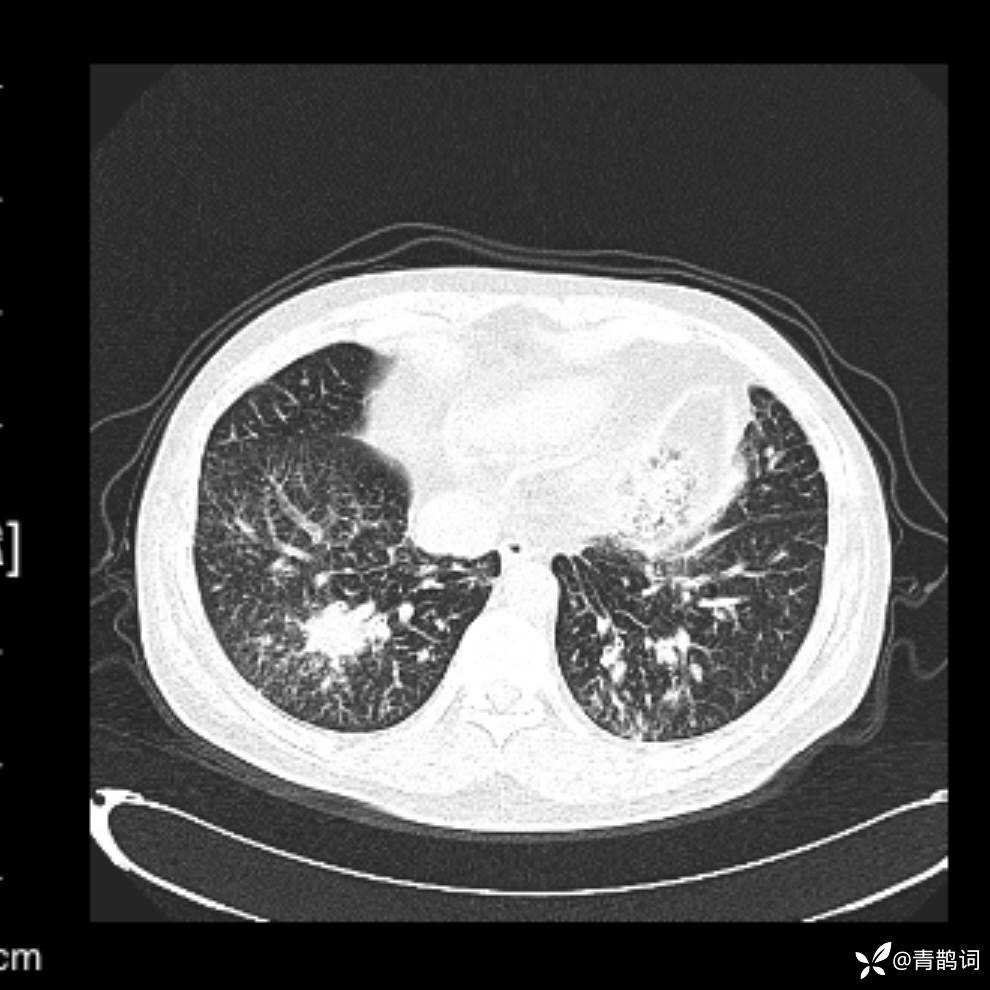

患者年龄:30岁。

患者性别:男。

简要病史:左颜面部肿胀2年,反复咳嗽咳痰,逐渐加重。

辅助检查